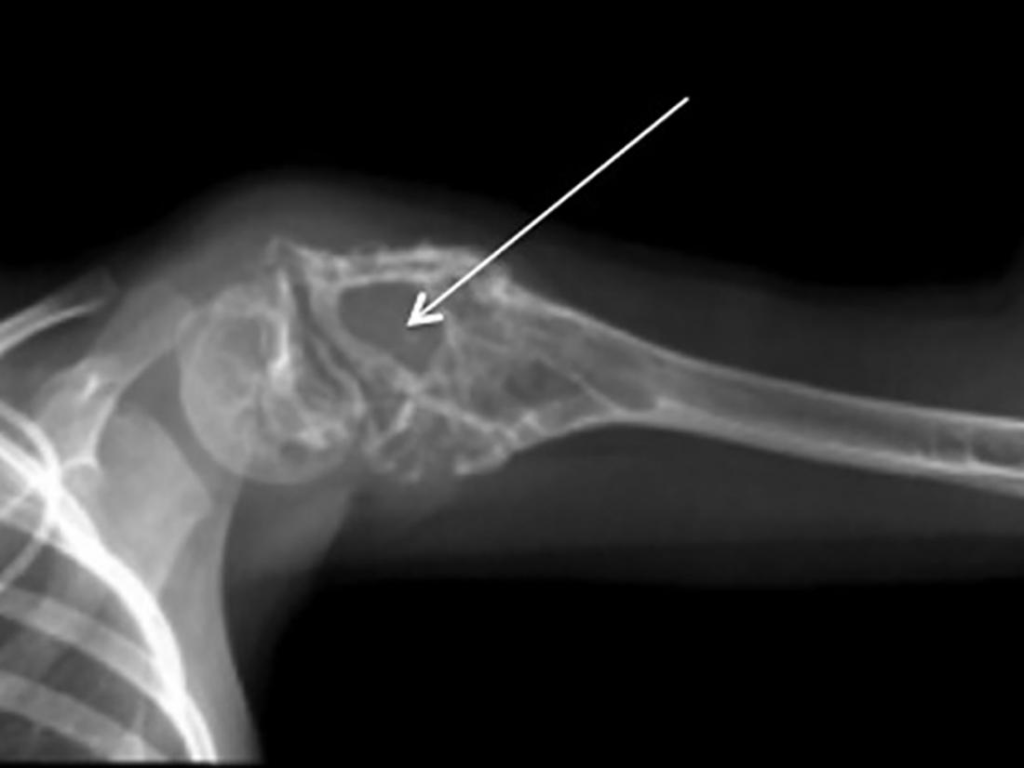

Diagnosing a tumor in the Ewing family involves a comprehensive approach that combines clinical evaluation and specialized diagnostic testing. The process often begins with imaging, starting with X-rays to visualize a palpable mass, and then moving onto more advanced techniques like CT scans, MRIs, and bone scans to determine the tumor’s size and check for metastasis to the lungs or other bones. A bone marrow biopsy may also be performed to see if the cancer has reached the marrow.

The definitive diagnosis is established through a surgical biopsy and histopathological evaluation of the affected tissue. Pathologists look for specific markers, such as the CD99 surface protein, which is present in the majority of Ewing family tumors. Additionally, molecular analysis plays a critical role; techniques like polymerase chain reaction allow researchers to amplify DNA sequences to identify the characteristic EWS-FLI1 translocation. These combined methods ensure an accurate identification of the tumor at a molecular level, which is essential for planning effective treatment.